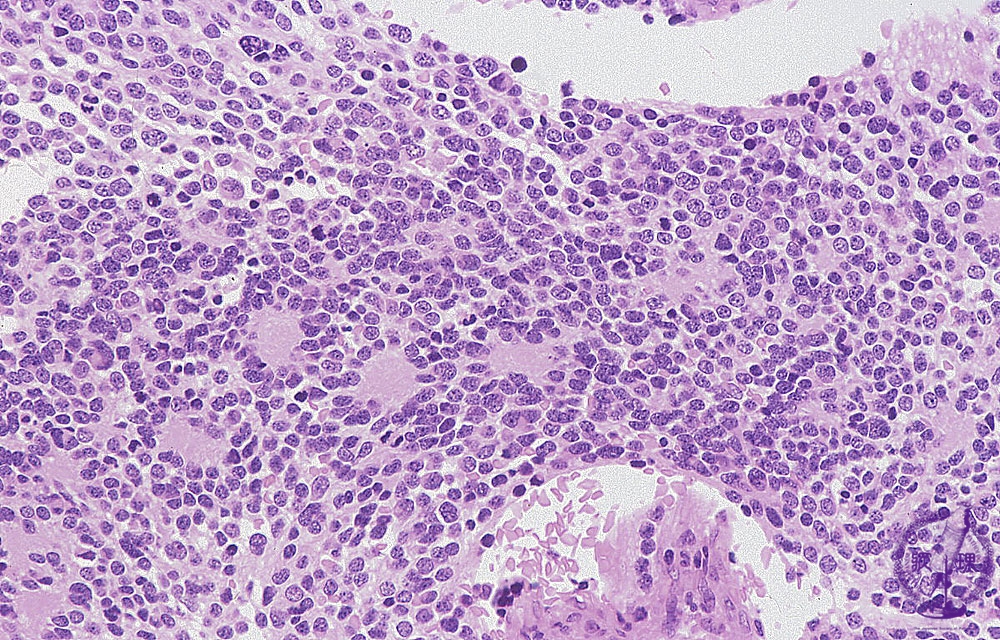

- ★(9)Peripheral neuroblastic tumors(poorly differentiated neuroblastoma)

Microscopic View; Small, primitive-appearing cells with dark nuclei, scant cytoplasm, high N/C ratio, and poorly defined cell borders growing in solid sheets. The tumor in composed of small cells embedded in a finely fibrillary matrix (neuropil) that corresponds to neuritic processes. Typically, rosettes (Homer-Wright pseudorosettes) can be found